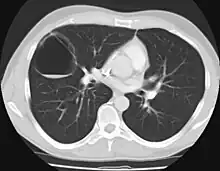

CPAMs are classified into three different types based largely on their gross appearance. Type I has a large (>2 cm) multiloculated cysts. Type II has smaller uniform cysts. Type III is not grossly cystic, referred to as the "adenomatoid" type. Microscopically, the lesions are not true cysts, but communicate with the surrounding parenchyma. Some lesions have an abnormal connection to a blood vessel from an aorta and are referred to as "hybrid lesions."

Imaging

The earliest point at which a CPAM can be detected is by prenatal ultrasound. The classic description is of an echogenic lung mass that gradually disappears over subsequent ultrasounds. The disappearance is due to the malformation becoming filled with fluid over the course of the gestation, allowing the ultrasound waves to penetrate it more easily and rendering it invisible on sonographic imaging. When a CPAM is rapidly growing, either solid or with a dominant cyst, they have a higher incidence of developing venous outflow obstruction, cardiac failure and ultimately hydrops fetalis. If hydrops is not present, the fetus has a 95% chance of survival. When hydrops is present, risk of fetal demise is much greater without in utero surgery to correct the pathophysiology. The greatest period of growth is during the end of the second trimester, between 20–26 weeks.

A measure of mass volume divided by head circumference, termed cystic adenomatoid malformation volume ratio (CVR) has been developed to predict the risk of hydrops. The lung mass volume is determined using the formula (length × width × anteroposterior diameter ÷ 2), divided by head circumference. With a CVR greater than 1.6 being considered high risk. Fetuses with a CVR less than 1.6 and without a dominant cyst have less than a 3% risk of hydrops. After delivery, if the patient is symptomatic, resection is mandated. If the infant is asymptomatic, the need for resection is a subject of debate, though it is usually recommended. Development of recurrent infections, rhabdomyosarcoma, adenocarcinomas in situ within the lung malformation have been reported.[4]